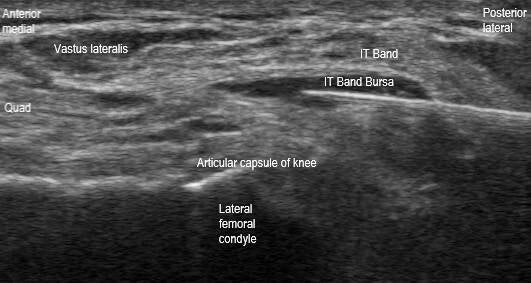

This is a transverse plane image short axis to the distal iliotibial (IT) band at the distal femur during an IT band bursa injection in a patient with a total knee arthroplasty (TKA). The needle can be seen in a posterolateral to anteromedial in-plane orientation with the needle tip within the IT band bursa. IT band friction syndrome is a common cause of overuse lateral knee pain following a TKA. During this procedure, care should be taken to avoid injecting deep to the articular capsule (intraarticular).